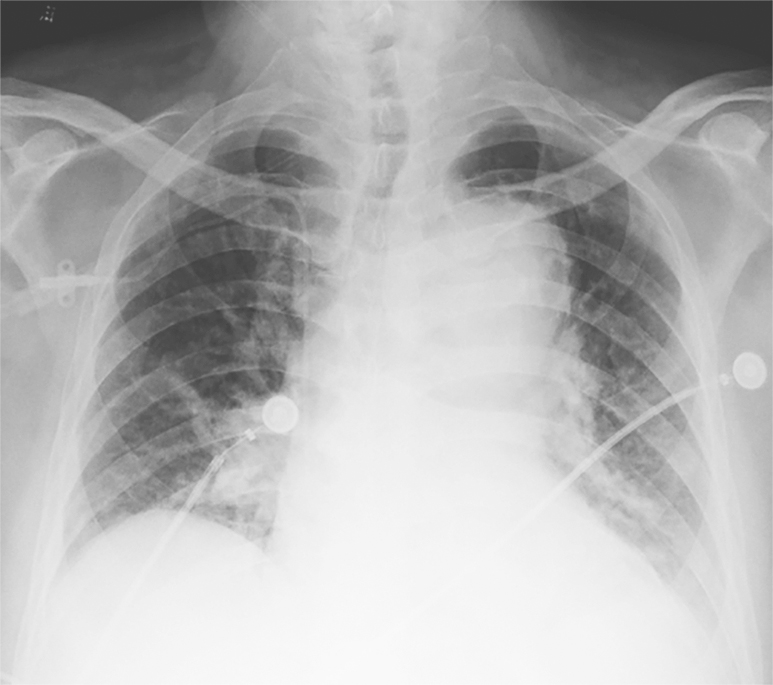

图4主动脉夹层导致纵隔影增宽

随着64层螺旋CT出现后,使冠状动脉、肺动脉及主动脉血管同时成像成为可能,即一站式多层螺旋CT检查。多排螺旋CT具有无创、快速等优势,并且具有丰富的图像后处理软件,是急性胸痛三联征的病因筛查及确诊的有效手段,具有卓越的临床应用价值。该检查技术就是扩大胸部扫描范围,调整扫描参数和对比剂注射量及注射速度,同时得到主动脉、冠状动脉及肺动脉影像信息,影像医师应用工作站进行图像后处理,可以运用曲面重建(curved planar reconstruction,CPR)、最大密度投影(maximum intensity projection,MIP)、多平面重建(multi-planar reconstruction,MPR)、容积再现(volume rendering,VR)等对冠状动脉、肺动脉、主动脉及肺部进行观察。胸痛三联征一站式扫描技术的重点就是为急诊医师提供短时、高效、可靠的诊断信息,对降低患者并发症、病死率十分关键。《中国胸痛中心认证标准》(第5版)规定:胸痛中心应具备多排螺旋CT增强扫描的条件,并能开展急诊主动脉、肺动脉CTA检查,从启动CT室到接受患者进行检查的时间在30分钟以内。恰当运用多层螺旋CT检测不仅可以明确危及生命的胸部动脉疾病原因,指导治疗,还可以实现非常高的潜在的成本效益。主动脉夹层在影像学上典型的表现如图4。